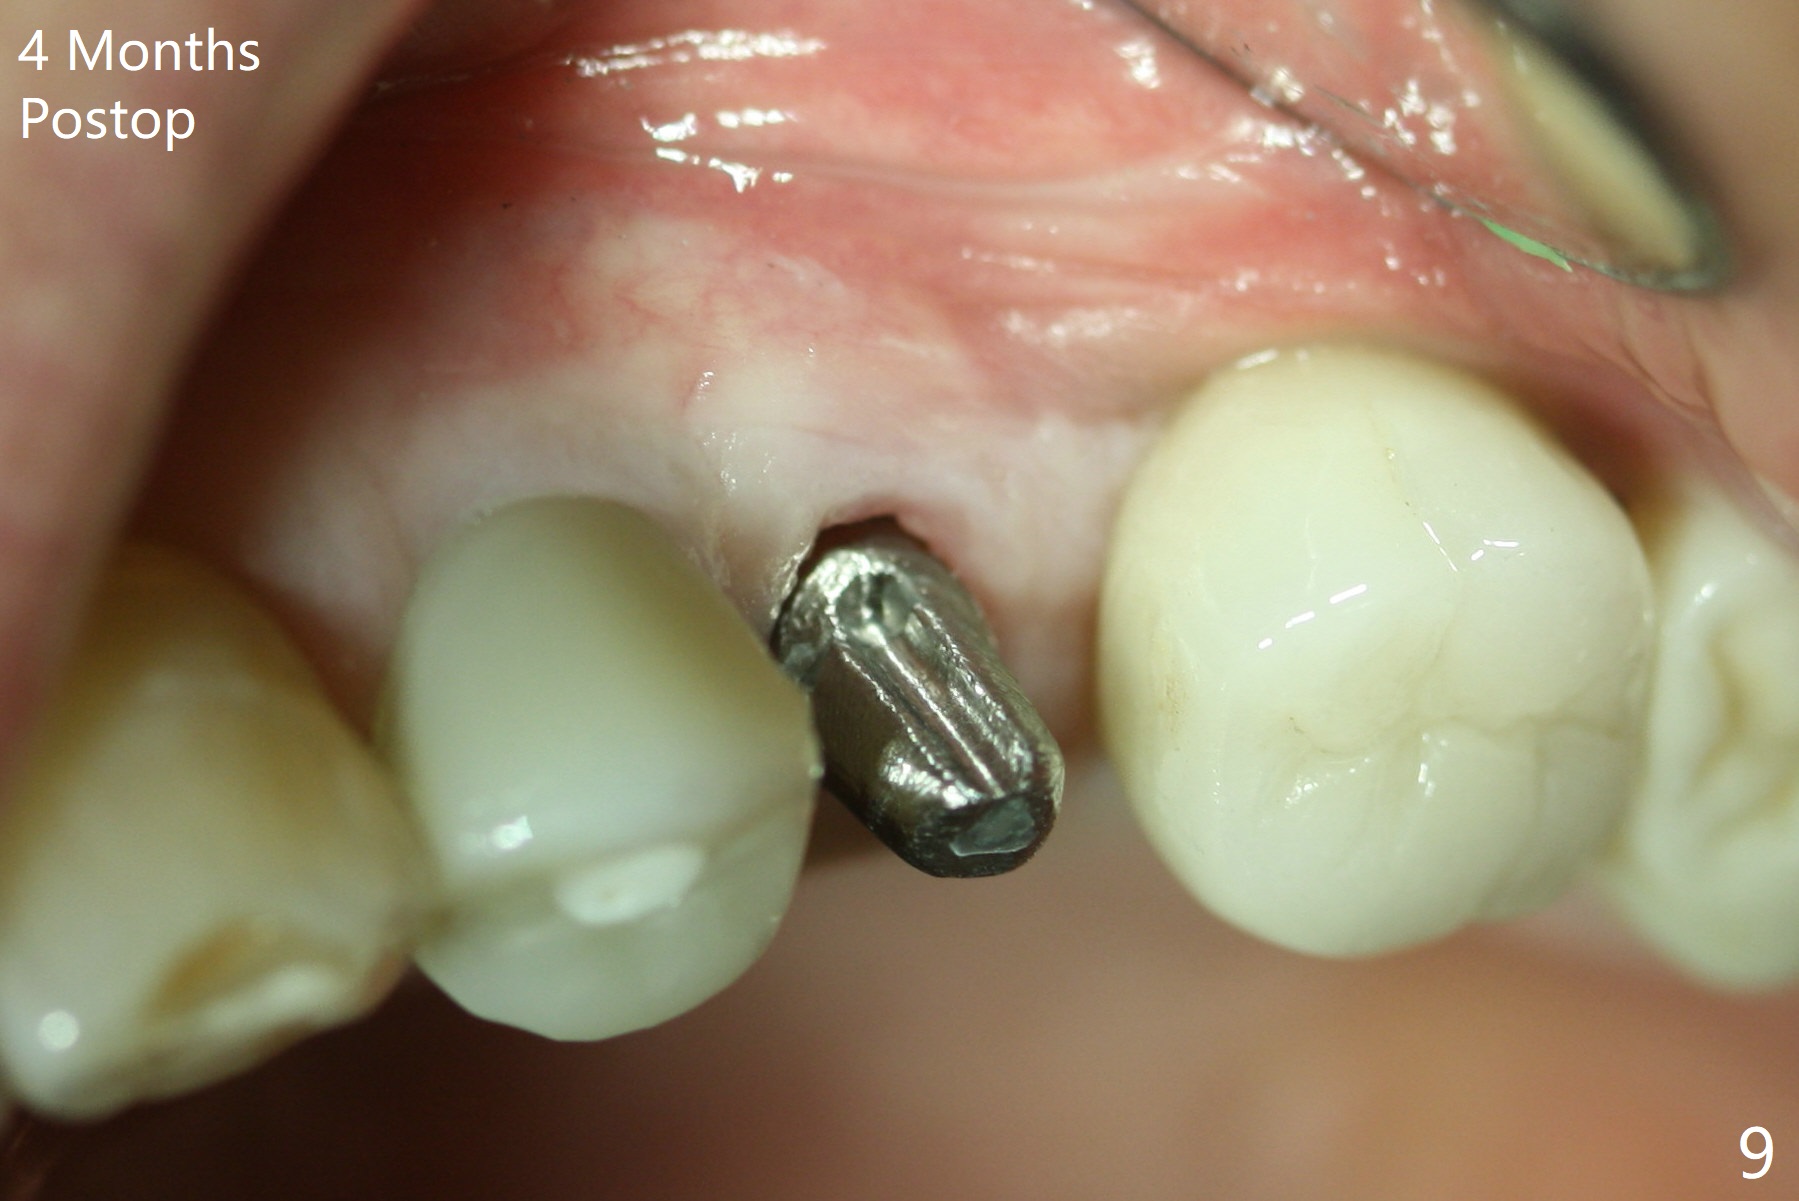

When the tooth #13 with buccal fistula is extracted, the root is found to have vertical fracture (Fig.1). The socket is 14 mm deep (gingival level); the initial osteotomy depth is 20 mm (6 mm to be in the native bone for primary stability, Fig.2). A 4.5x20 mm tissue-level implant (>60 Ncm) is going to be placed in the palatal aspect of the oval socket (Fig.3-5). The localized defect in the buccal plate as indicated by labels (* (Vanilla/Osteogen), B (buccal) and < (perforation) in Fig.6,7 (CBCT coronal and axial sections) is repaired by the bone graft. The bone and gingiva are healthy around the implant nearly 4 months postop (Fig.8,9).